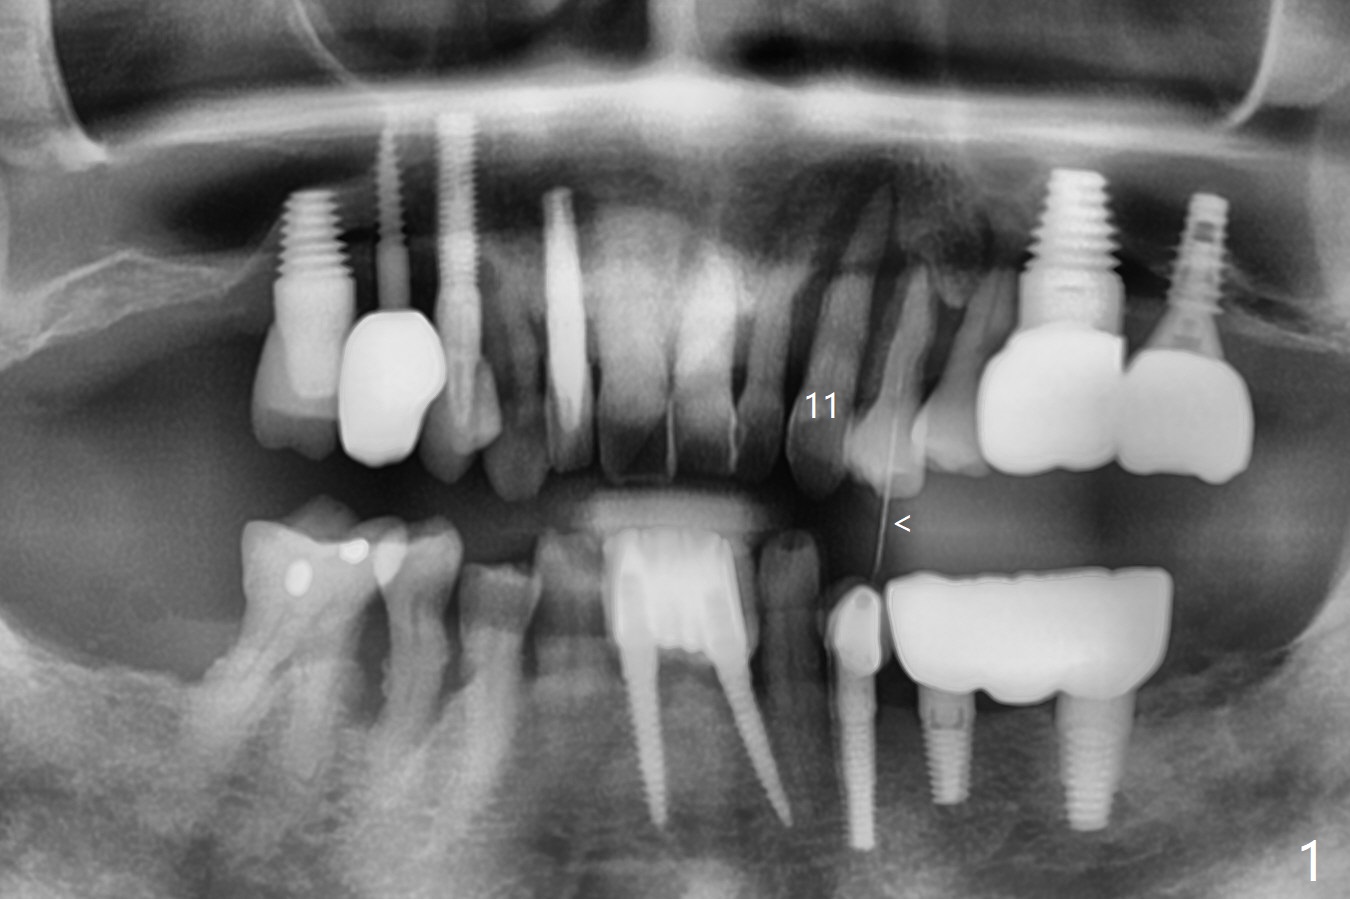

A 62-year-old man with generalized chronic periodontitis returns with chief complaint of loose tooth at #11 (Fig.1). Although a buccal fistula (Fig.1 <) is closer to #12 than to #11, percussion is more severe at #11 than 12. The buccal plate of #11 is missing, but it is possible to place a narrow immediate implant because of the wide alveolus (Fig.2). Since the gingiva is ~ 10 mm long, a mill abutment is to be used (Fig.3,5). In fact the fistula communicates with #11 extraction socket. After debridement, osteotomy is initiated (Fig.4) for a 3.8x10 mm implant ~ 35 Ncm, followed by seating a 4.5x2 mm mill abutment (Fig.5). Abundant sticky bone is placed in the remaining socket (for buccal plate reconstruction) and against the root surface of the neighboring teeth (Fig. 6 * (#10,12)). Finally 2 pieces of PRF membranes are utilized to facilitate repair of the buccal soft tissue defect (Fig.7 *). The root prominence of the canine seems to be maintained by the bone graft (Fig.8 C). Acrylic dressing holding the PRF membranes in place remains in situ with the healthy gingiva buccal (Fig.9) and palatal (Fig.10) 11 days postop. Note the acrylic locking into the undercuts of the neighboring teeth (*). 经过一段摸索发现离心每分钟1500转5分钟后,抽取上清液,接着再离心10分钟剩余上清液就形成血小板块,压制后便是血小板膜,后者似乎有助于软组织愈合,而上清液用来制备骨块,帮助硬组织生长。利用这个原则讨论以下病例治疗。The gingival margin gains ~ 5 mm 6 weeks postop when the acrylic dressing is removed (Fig.11,12 (<: previous one), as compared to Fig.7,8). 治疗结束时尖牙牙龈缘高于第一双尖牙(图七,八),六个星期后,尖牙牙龈缘却低于双尖牙(图十一,十二(箭头:原始牙龈缘))。术后2.5,4.5月基台周围牙龈似乎能与钛合金附着,防止细菌进入深部植体(图十三,十四)。临时牙冠脱落多次,可能与mill abutment太光滑有关,所以颊侧,舌侧磨成平面(图十四)。取模时好像不必取出基台清洗(仿佛没有炎症),原位用树脂延长基台。术后5个月CT显示颊侧骨板再生(图十六-十八)。取模时并没有用树脂加长基台;粘固时,牙冠颜色理想,但是照片中并不是如此(图十九,二十),颊侧骨板没有塌陷。术后11个月基台颊侧骨板没有萎缩(图二十一:B);3d图像:骨壁完全形成(图十六对比:部分形成)。密度也增高(图二十二:B),与术后五个月比较(图十七)。术后十一个月,粘固后五个月角化龈存在(图二十三),牙冠颈部有金属颜色透出,是因为二段式基台太粗了(最细4.5毫米),可以请实验室在牙冠内部涂opaque material而减轻。